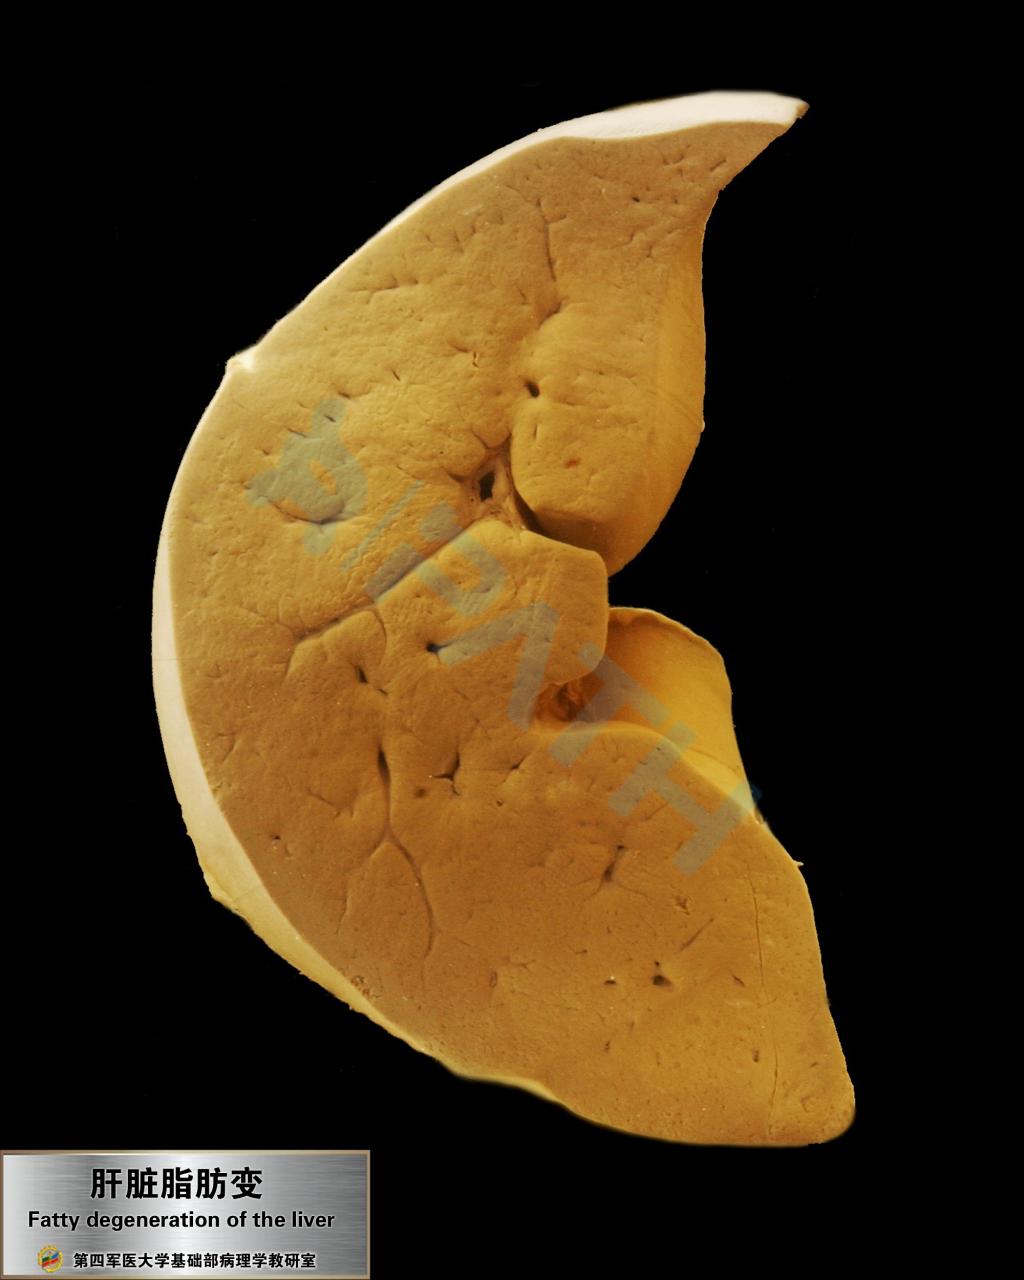

肝脂肪变性